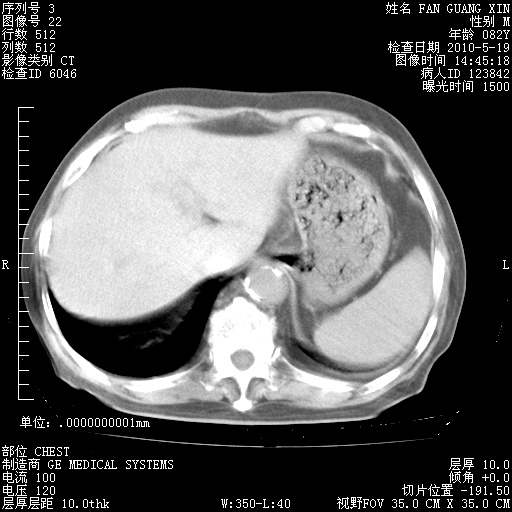

治疗3周后的肺部CT纵隔窗

再治疗10天后的肺部CT

阅读此次胸部CT,肺间质渗出性改变较入院时有吸收。目前从体温、白细胞、中性分叶明显增高,肯定存在细菌感染(发生医院感染哦,若无消化道及泌尿系统等感染的依据,肺部感染可能大)。若你院头孢哌酮舒巴坦钠耐药率较高,同意你的方案,若48小时体温仍高,可考虑使用碳青霉稀类抗菌药物,同时可予超声雾化、注意滴数时加大液体量。白蛋白33.30g/L较低哦,需加强营养等支持治疗。